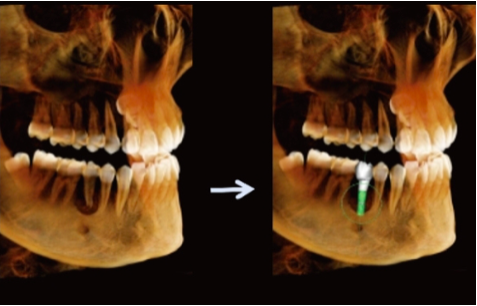

Simulação de Extração Dentária e Óssea – Planeamento de Implante Imediato

Permite a extração do dente comprometido e a sua substituição por um implante adequado na simulação.

Melhora a comunicação entre médico e paciente, permitindo ao paciente visualizar o resultado final do implante antes da extração.